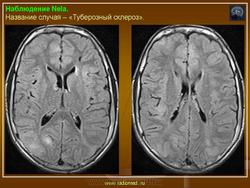

Туберозный склероз (болезнь Бурневилля-Прингла, синдром Бурневилля - Брессау) - глиоз белого вещества мозга, проявляющийся в раннем детстве эпилептическими припадками (в 85%), олигофренией в сочетании с нараста­ющей пирамидной и экстрапирамидной симптоматикой, кожной патологией. В возрасте 4-6 лет на лице в форме бабочки в области носа обычно появляют­ся множественные желто-розовые или коричнево-красные узелки диаметром чуть больше 1 мм - аденомы Прингла, которые обычно признаются аденомами сальных желез, однако есть мнение и о том, что они представляют собой про­исходящую из нервных элементов кожи гамартрому.

На поверхности мозга наблюдаются единичные или множественные глиома-тозные узлы, по цвету несколько светлее окружающего мозга и плотнее его на ошупь, возможна их кальцификация. Узлы могут быть и в белом веществе, под­корковых ганглиях, а также в стволе мозга и в мозжечке.

Встречаются и аномалии развития извилин мозга в виде микро- и пахигирии. Заболевание чаще носит спорадический характер. Бляшки достигают диаметра 5-20 мм. В коре больших полушарий и мозжечка иногда могут быть обнару­жены пластинчатые тельца, напоминающие амилоид. Происходит дегенерация клеток коры. При КТ-исследовании головы нередко можно выявить кальцифика-ты и глиальные узелки в паравентрикулярной области, субэпендимарно вдоль на­ружных стенок боковых желудочков, в зоне межжелудочкового отверстия Мон­ро, реже - в мозговой паренхиме. На М РТ головного мозга в 60% выявляются гипотеденсивные очаги в одной или обеих затылочных долях, которые расце­ниваются как участки неправильной миелинизации (Козлов А.В., 2002).